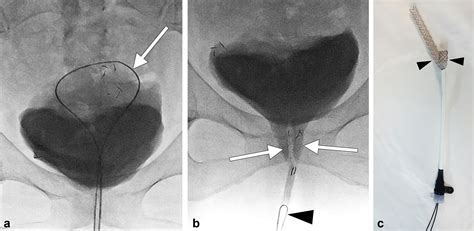

• Removal using a cystoscope: If the stent does not have a string attached, the doctor will use a cystoscope—a thin, lighted tube with a camera. This is inserted through the urethra into the bladder to visualize and grasp the stent, which is then pulled out.

• Removal via a pull-string: Some stents are placed with an external string extending from the urethra. In this case, the removal is much faster, often taking just a few seconds as the doctor simply pulls the string to slide the stent out.